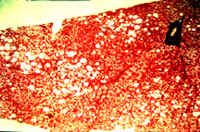

8-4-10.jpg (66313 bytes)

Fig. 8-4-10. Another case, advanced lesion.

In this case the lesion is more advanced: there id ballooning degeneration, cell

necrosis, nuclear changes, fine cholestasis and beginning fibrosis,